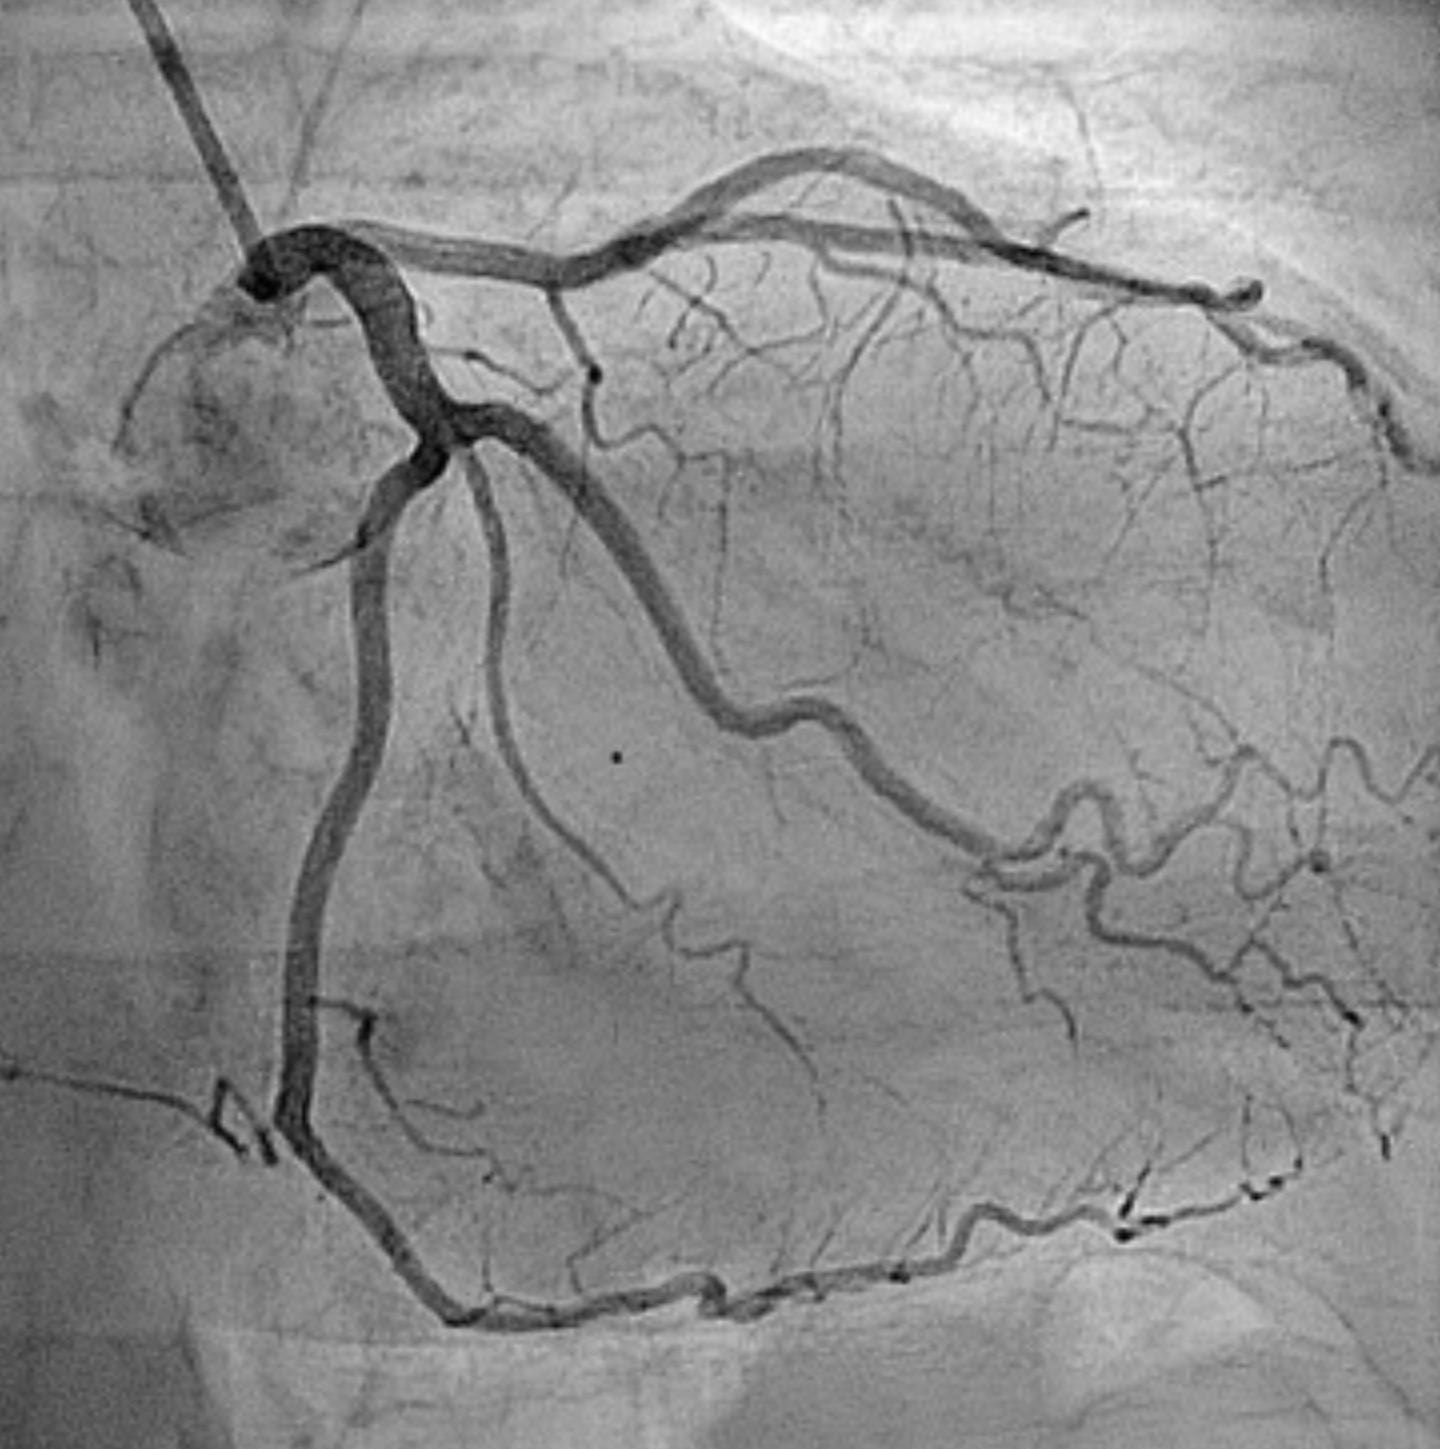

John Roe has plaque but no symptoms. He ended up getting an angiogram a few years ago for chest pain that ultimately turned out to be acid reflux. But somebody put him on 80 mg of atorvastatin.

He had wanted to know what his lipid numbers were, so we checked them. They were quite low. His LDL was 42. For people who believe in target numbers, under 70 is the desired target for patients with known heart disease. Would John qualify as a member of that population?